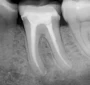

The aim of root canal therapy is to remove all the toxins and debris that has formed by bacteria from the canal. The inside of the tooth is cleaned and disinfected so that it is prepared for a root canal filling. The highly qualified and professional dentist carefully files the canals with profile rotating instruments and during this process, we constantly wash the canals and disinfect them.

Root Canal Treatment Dentists South Africa

Location of the canals are sometimes a challenge. We work with Dental Loupes that gives magnification and digital xrays and apex locators to ensure the best accuracy, 3D xrays are sometimes also indicated to assess the situation. As an added disinfection we use laser energy to kill of the bacteria, this also gives excellent pain relief. After a session of filing and cleaning the canal, and the patient is symptom free, the canal is then filled with a rubber-like material called Gutta-Percha.

To protect the tooth, we then restore it with a crown or filling. After restoration, the tooth continues to function like any other tooth. This procedure is done with local anaesthetic and can be completely pain free. In some severe septic cases, the anaesthetic may not be very effective and the patient may have discomfort or pain initially but this occurs infrequently. In some cases where the tooth is severely infected a course of antibiotics might be needed.